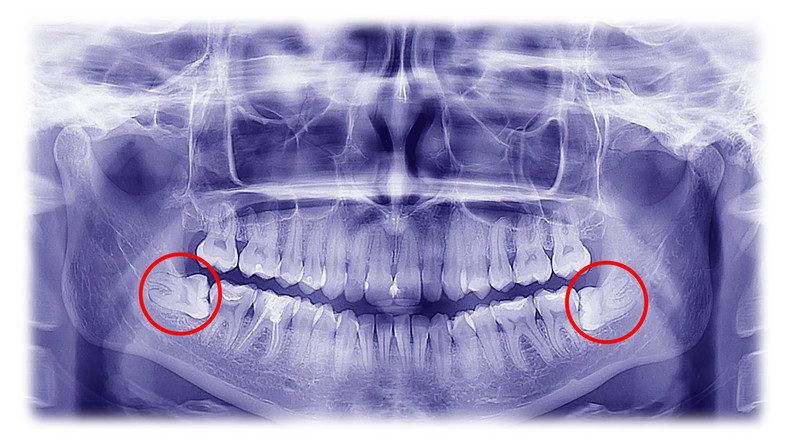

A tudósok szerint még sosem voltak ennyire forró nyomon az Alzheimer kialakulásának okait keresve, és a bizonyítékok a fogainkhoz vezették őket. Pontosabban egy ínybetegség lehet az, ami kiváltja a visszafordíthatatlan agyi leépülést.

Ez nem az első alkalom, hogy az emberek szájára terelődött a gyanú, de most már egérkísérletek is megmutatták, hogy a szájfertőzés szorosan összefügg az agyra kiterjedő kórral.

Eddig is kérdés volt, hogy egy szájbetegség okozza-e az Alzheimert, vagy a már kialakult betegség vezet-e a fogak romlásához, de most úgy látszik, hogy a korábbi igazolódott be.